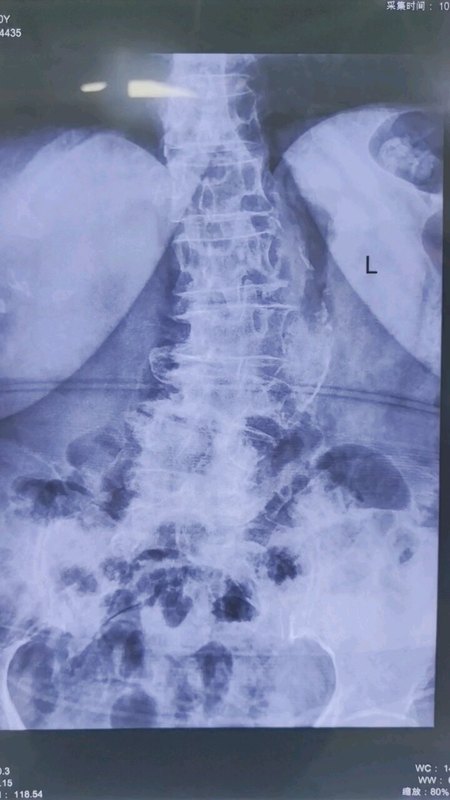

腰椎管狭窄症是许多老年人都会得的病,许多子女也都很担心父母的这种情况,会在网络上多了解一些这方面的知识,久而久之,不少患者和家属也都会自己简单看个片子,知道自己大概要做哪种治疗。但了解的多了,疑惑就多了,“为啥医生说的和网上不一样?”、“我自己看片子也不严重,怎么就让手术?这是不是忽悠我呢?”其实,许多患者朋友只知其一不知其二,和临床医生相比了解还是不够深入。最近,一位63岁的男性患者在家人的陪伴下来到宣武医院王作伟主任的门诊。他在4年前就出现了腿疼的症状,然后去当地医院就查出来是腰椎管狭窄,当时感觉还不是特别严重,就做了保守治疗。可之后他的症状反复加重,尤其是走路距离远一些的时候,小腿肚子特别疼,不得不停下来缓一缓再走。这期间,他自己没事就在网上看看相关知识,也试了许多方法,但效果都不明显。尤其是近几周,他感到症状加重了许多,走路不到100米就疼得受不了,再次去当地医院后,建议他进行手术。这让他不敢相信,“我自己看片子也没那么严重,咋要手术?”于是为了进一步治疗,他们一家来到北京想找专家再看看,最后来到王主任门诊。王主任仔细询问他的病史,发现他的症状还是比较典型的,然后又看了他的片子后,发现上面显示的情况并没有他说的那么轻。原来,我们做核磁共振检查后一般会给一张矢状位片子和一张轴位片子,从这位患者的片子上看,矢状位片子上椎管狭窄可能没有特别严重,但在轴位片子上显示腰椎管已经被严重挤压,里面的神经也被压得厉害。术前影像学资料:许多患者就不懂了,“我也会看片子,就是脊柱椎体后面那个浅色的长条是椎管,不就是看这里有没有狭窄吗?”其实,大家经常看的或者容易看懂的片子是矢状位的,但很多患者都忽略了或看不懂轴位片。事实上,腰椎的核磁共振片子是许多腰椎疾病诊断中必不可少的一项检查。我们可以把它简单理解成从不同角度的切片,其中矢状位相当于从正面向背面方向竖着的切片,而轴位是水平方向的横截面。所以我们在看片子时要看全面,千万不要只看一面。而腰椎管狭窄是否手术也并非光看看片子就能决定,还需要结合患者的具体症状、病史、查体等检查结果一起综合考虑。比如这位患者的情况,他的病史很长,保守治疗没有效果,腰椎管在腰4-5节段明显狭窄,症状严重影响日常生活,王主任建议他可以通过手术改善今后的生活质量。在获得患者同意后,王主任为他成功进行了腰椎管减压手术。术后,他的腿疼症状立马得到了明显减轻,腿麻的情况也在好转,出院时已经可以独立行走了。术后影像学资料:许多患者都以为久病能成医,但事实上却一知半解。大家也要知道在网上光发张片子咨询,并不能得到准确的治疗方案,还是需要去正规医院做相关查体等检查,医生会根据您的具体情况综合评估,给出个体化的治疗方案。

腰椎管狭窄:警惕中老年人腰腿痛的“幕后黑手”

在日常生活中,许多中老年人常被腰腿痛困扰,其中腰椎管狭窄症是常见原因之一。它是指腰椎的椎管、神经根管或椎间孔的狭窄,压迫神经根或脊髓,引发一系列症状。腰椎管狭窄症多因长期劳损、腰椎退变、骨质增生、椎间盘突出等因素导致。患者常表现为腰痛、下肢疼痛、麻木、乏力,甚至间歇性跛行。比如,患者行走一段距离后,腿部酸胀无力,需蹲下或坐下休息片刻才能缓解,这是由于行走时神经根受压加重,休息后压迫减轻所致。诊断腰椎管狭窄症主要依靠病史、体格检查及影像学检查。X光可观察腰椎骨质增生、椎间隙狭窄;CT和MRI能清晰显示椎管狭窄程度及神经受压情况。治疗上,轻中度患者可选择保守治疗,如卧床休息、佩戴腰围、物理治疗、药物治疗等,缓解症状。对于症状严重、保守治疗无效者,可通过手术治疗,手术方式包括脊柱内镜微创手术和开放手术。而老年人往往基础疾病及合并症较多,使得其全身麻醉和开放手术的风险明显升高。目前脊柱内镜手术因其创伤小、恢复快,局麻下即可完成手术,越来越得到临床医生和患者的青睐。预防腰椎管狭窄症,需从日常做起。保持正确姿势,避免长时间弯腰、久坐;加强腰背肌锻炼,增强脊柱稳定性;控制体重,减轻腰椎负担。若出现腰腿痛症状,应及时就医,明确病因,避免延误治疗,提高生活质量。